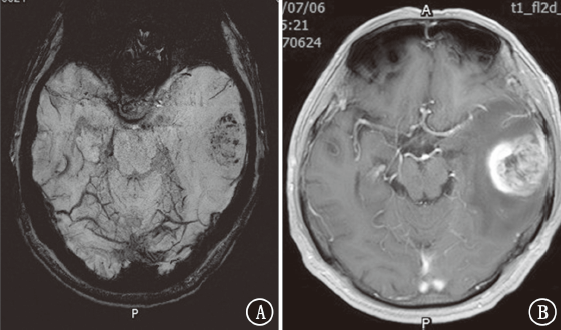

目的探讨磁敏感加权成像(SWI)在颅内转移瘤中的鉴别诊断价值。方法收集2018年 1月至2020年4月新疆维吾尔自治区人民医院住院患者中原发肿瘤为肺癌、乳腺癌、肾癌、直肠癌、膀胱癌、黑色素瘤的颅内转移瘤及胶质母细胞瘤患者63例,半定量评估肿瘤内的敏感性信号强度(ITSS)分级。比较颅内转移瘤与胶质母细胞瘤ITSS分级。结果81个颅内转移瘤中,0级为36个(44.4%),Ⅰ级为25个(30.9%),Ⅱ级为14个(17.3%),Ⅲ级为6个(7.4%);27个胶质母细胞瘤均为Ⅱ~Ⅲ级(100%)。肺癌转移瘤0~Ⅰ级占73.6%(28/38),乳腺癌转移瘤0级占84.6%(22/26),肾癌转移瘤Ⅱ级占5/6,直肠癌转移瘤0~Ⅰ级占4/5,胶质母细胞瘤Ⅲ级占77.8%(21/27)。颅内转移瘤与胶质母细胞瘤ITSS分级组间差异有统计学意义(Z=7.013,P<0.001)。采用受试者工作特征曲线分析显示,ITSS≤Ⅰ级判断颅内转移瘤的敏感性为100%,特异性为75.3%,曲线下面积为0.936(95%CI为0.891~0.980,P<0.001)。结论颅内转移瘤ITSS分级多表现为0~Ⅰ级,胶质母细胞瘤多表现为Ⅱ~Ⅲ级。SWI在颅内转移瘤中有一定的鉴别诊断价值。